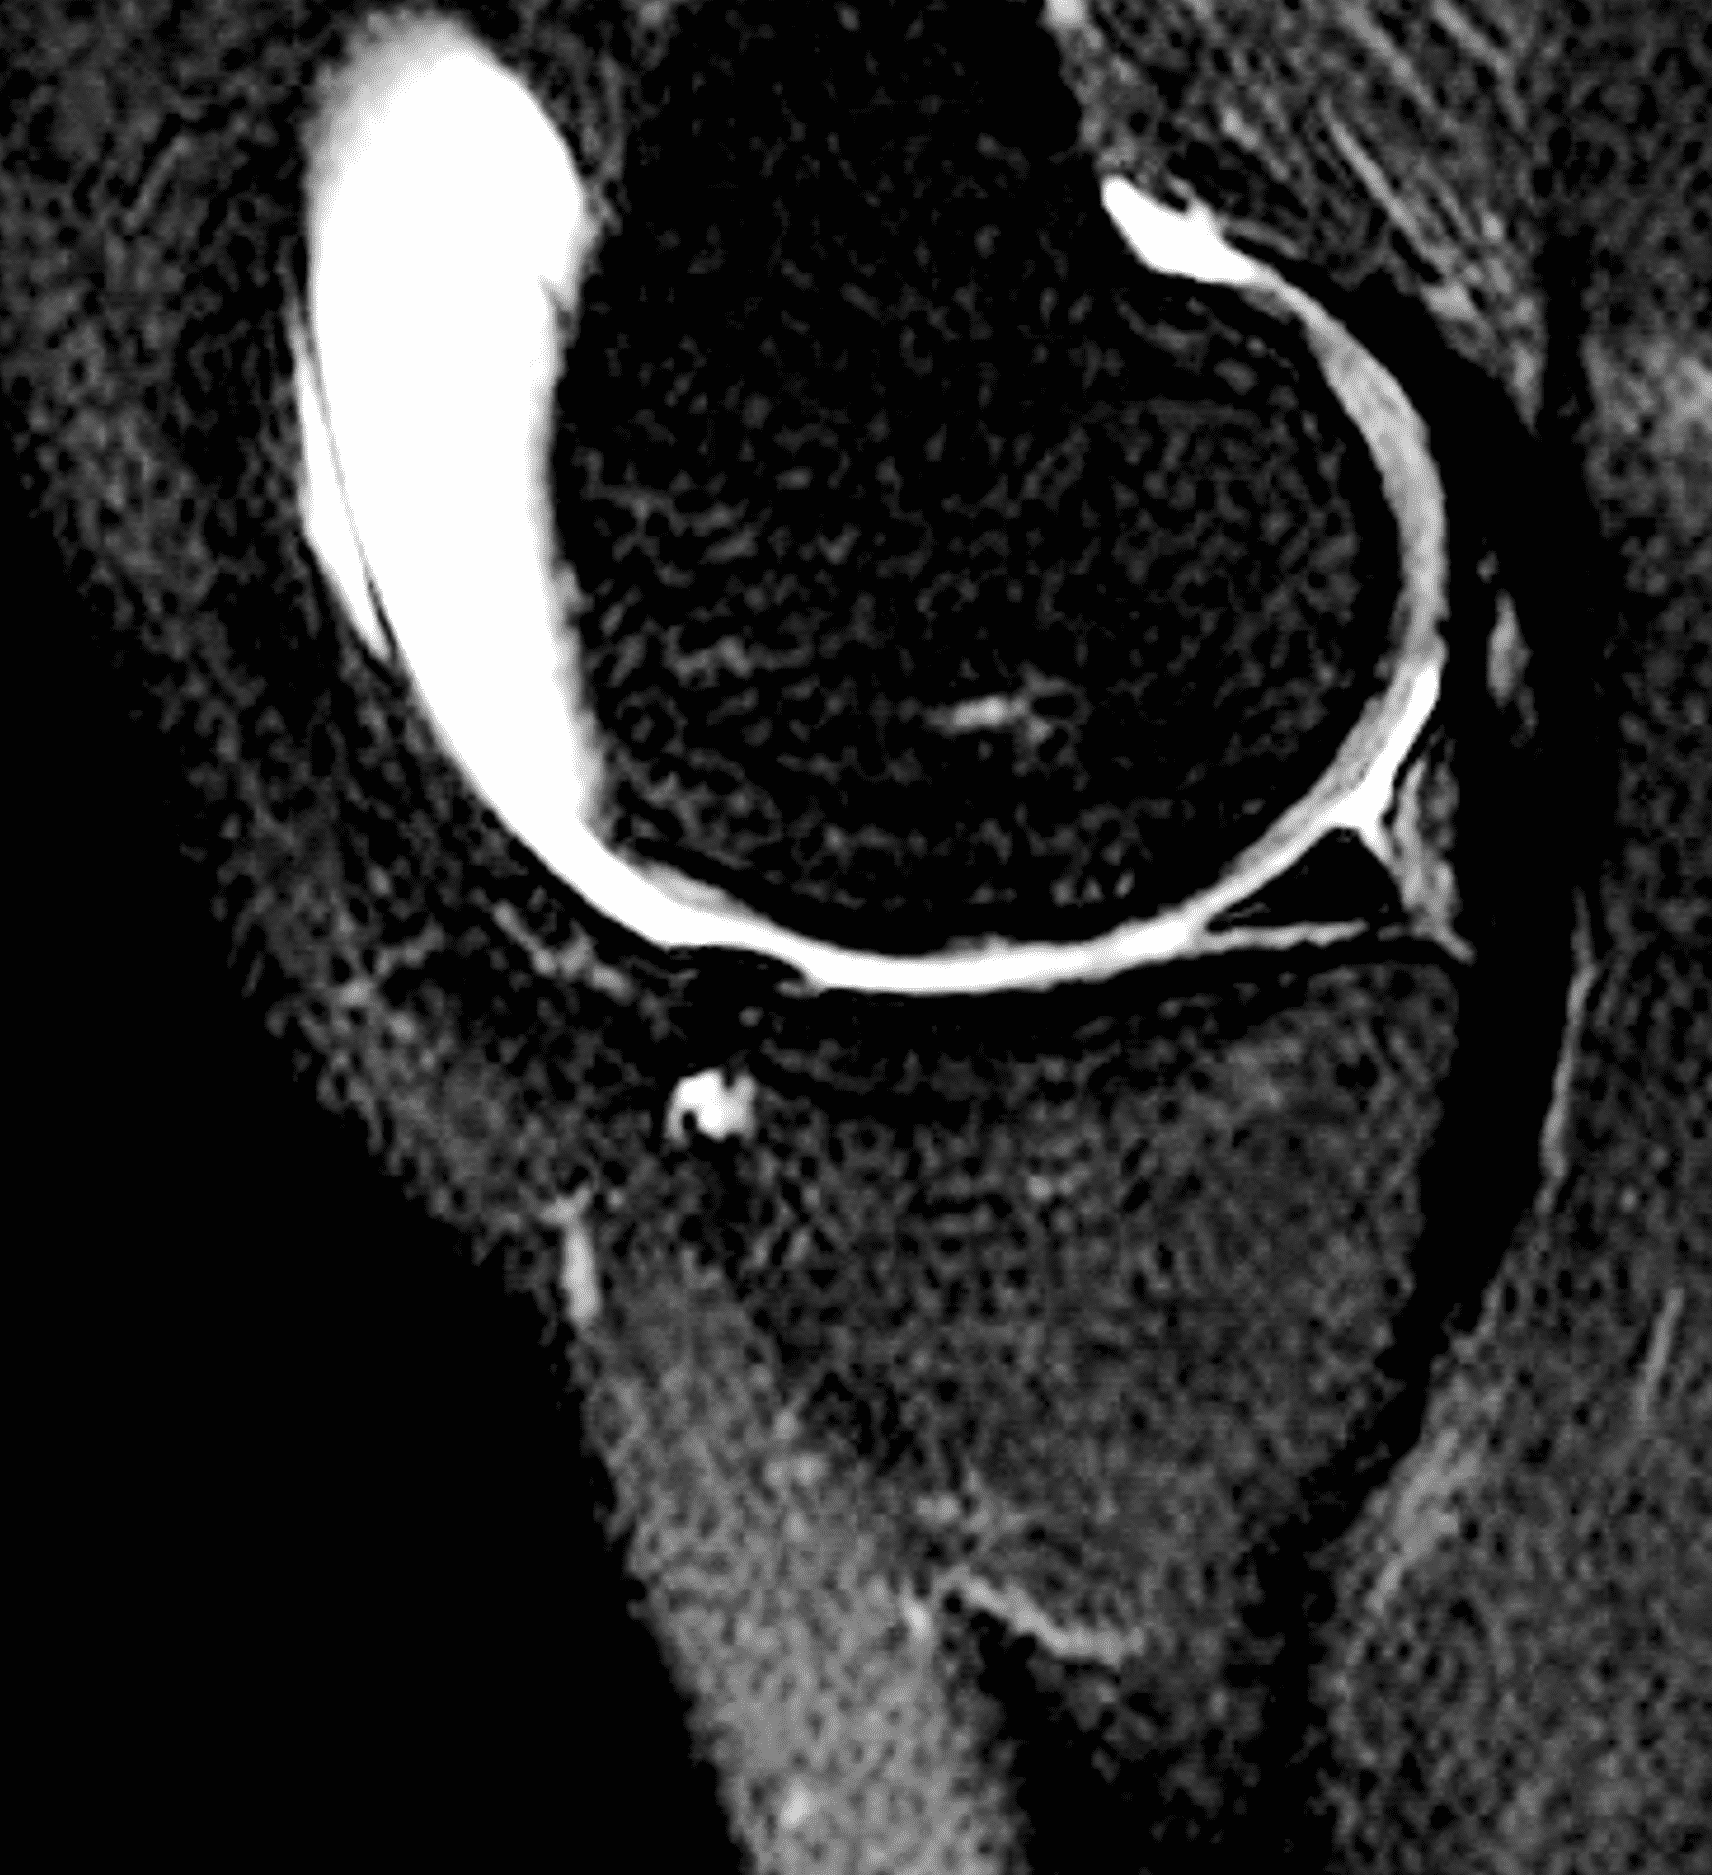

A 32-year-old man suffered a traumatic chondral injury to the medial femoral condyle that was treated with an osteochondral allograft 20 months previously. Representative images from a current knee MRI include (1A) coronal fat-suppressed fluid-sensitive and sagittal (1B) T1-weighted, (1C) proton density-weighted, and (1D) T2-weighted sequences. Are the post-operative MRI findings normal and expected, or abnormal and pathologic? Based on these images, would you characterize the procedure as a success or failure?

Figure 2: (2A) On the coronal image, the margins of the osteochondral graft are faintly visible (arrowheads). Both the graft and underlying bone show mild marrow edema, an expected finding. (2B) The T1-weighted image shows continuity of the marrow in the graft (asterisks) with the underlying bone, indicating osseous integration. A bioabsorbable pin (arrow) used for graft fixation is partly visible. (2C) The proton density-weighted image shows a low signal intensity seam (black arrow) between the native cartilage and transplant, as well as a defect in the subchondral bone plate of the graft (red arrow) where the pin was drilled, both normal findings. (2D) The T2-weighted image shows a smooth, congruent articular surface (arrows), restoring the normal anatomy, and a tiny subchondral cyst. No findings are present to suggest graft failure. The patient’s current symptoms were attributed to pathology elsewhere in the joint (not shown).

The postoperative imaging appearance of osteochondral allografts is similar to autografts (Figure 2).33 The subchondral bone plate of the donor and recipient sites do not have to match, but the articular surface should be congruent. Grafts that fail to incorporate by one year have a poor prognosis. Persistent marrow edema (beyond 12 months), a thick graft interface containing cysts or fluid, and subsidence of the graft are associated with poor osseous healing and worse outcomes. Extensive host marrow edema and severe synovitis may be a clue to immunologic rejection of the graft (Figure 18).21, 34